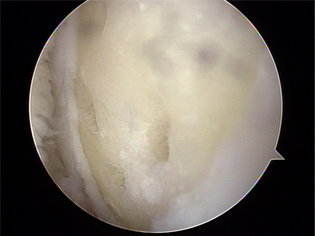

대부분 관절경으로 치료하며, 변연절제술을 하게 됩니다. 일시적인 효과는 있지만 퇴행성 진행을 지연시키지 못해 통증이 재발하기 쉬우며 관절염이 더 빨리 진행 할수도 있습니다.

미세천공술 1